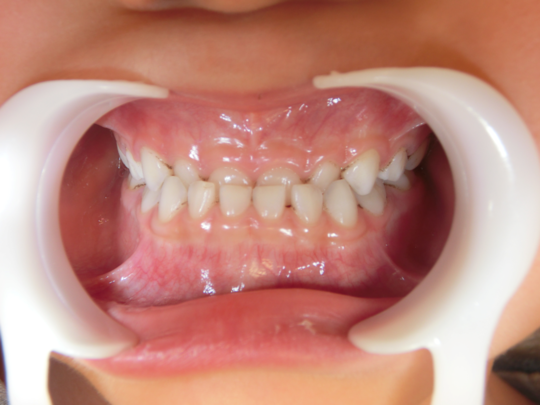

治療後

治療の副作用(リスク)歯の動き方には個人差があり、予想された治療期間が延長する可能性があります。。床矯正の使用状況、矯正歯科治療には患者さんの協力が必要であり、それらが治療結果や治療期間に影響します2次矯正が必要になる場合もあります。